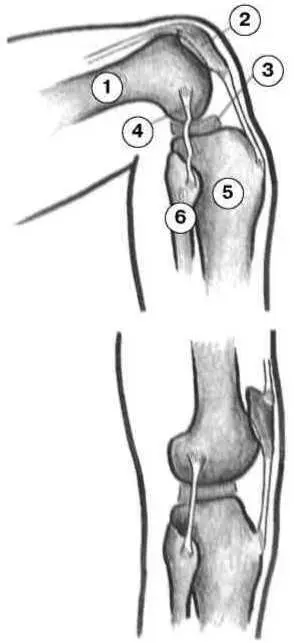

По отношению к колену ось бедра проходит не вертикально, а слегка наискось. Это обеспечивает большую устойчивость. Основные движения колена — сгибание и разгибание, кроме того, здесь возможно вращение внутрь и наружу, но только при сгибании, так как при разгибании боковые и крестовидные связки удерживают сустав (рис. 6.4).

Рис. 6.4. Тугие связки колена разгибании: 1 — бедро; 2 — коленная чашечка; 3 — мениск; 4 — наружная связка; 5 — большая берцовая кость; 6 — малая берцовая кость.

Коленный сустав соединяет бедро и большую берцовую кость. В качестве буфера в коленном суставе есть два клиновидных хрящевых диска. Это мениски. Они помогают смягчить давление на коленный сустав и перераспределить нагрузку. Таким образом, они защищают сустав. Хрящевой диск лежит внутри сухожилия и может скользить в нем. Малая берцовая кость прилегает к большой берцовой с внешней стороны сбоку. Здесь начинаются некоторые мышцы, поэтому при перенапряжении это место может оказаться очень чувствительно к изменению давления.